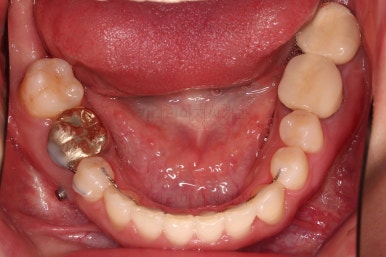

부산치과교정 키다리아저씨치과 초진 시 입안의 모습입니다.

확연히 좌우의 삐뚤어진 정도가 차이나죠.

덧니도 좌측(사진에서 보면 오른쪽) 위아래만 있는 상태고요.

좌측으로 삐뚤어져서 앞니도 좌측으로 쏠려 있는 상태였습니다.

우측만 위아래 뽑았지만 기능에는 문제 없이 교합을 마무리 했습니다.